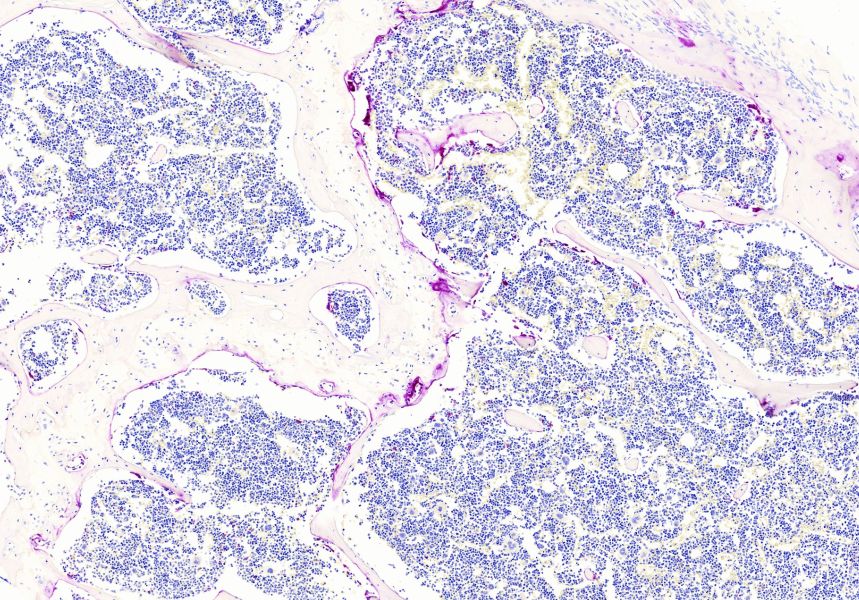

HE染色